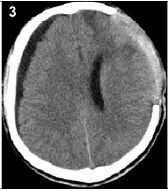

20160503094709

20160503094717

20160503094723

20160503094729